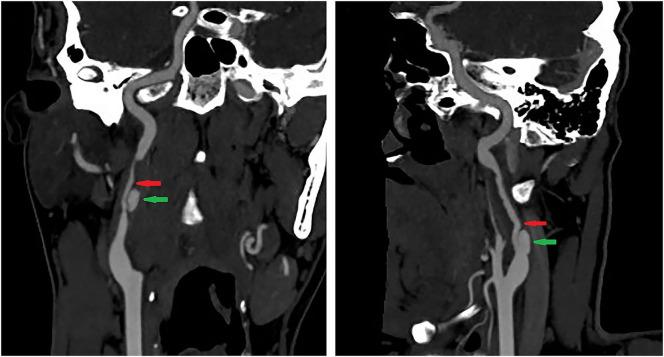

Internal carotid artery dissection (ICAD) results from a tear in the intima or rupture of the vasa vasorum with bleeding within the media resulting in separation of the vessel wall layers and a false lumen. It may cause arterial stenosis, occlusion, or dissecting pseudoaneurysm. Currently, the treatment of ICAD is controversial, including drug therapy and endovascular stent implantation. Simultaneous spontaneous dissection of bilateral carotid artery is rarely reported. We reported a 39-year-old-man with bilateral ICAD. Although the long-term durability of endovascular stent remains to be determined, for ICAD failed with active drug treatment and combined with hemodynamic impairment, early endovascular stent should be considered.

颈内动脉夹层(ICAD)是由于内膜撕裂或滋养血管破裂,血液在中膜内出血,导致血管壁各层分离并形成假腔。它可能导致动脉狭窄、闭塞或夹层假性动脉瘤。目前,ICAD的治疗存在争议,包括药物治疗和血管内支架植入。双侧颈动脉同时自发性夹层的报道很少。我们报告了一名39岁的双侧ICAD男性患者。尽管血管内支架的长期耐久性仍有待确定,但对于积极药物治疗失败且合并血流动力学损害的ICAD,应考虑早期进行血管内支架治疗。